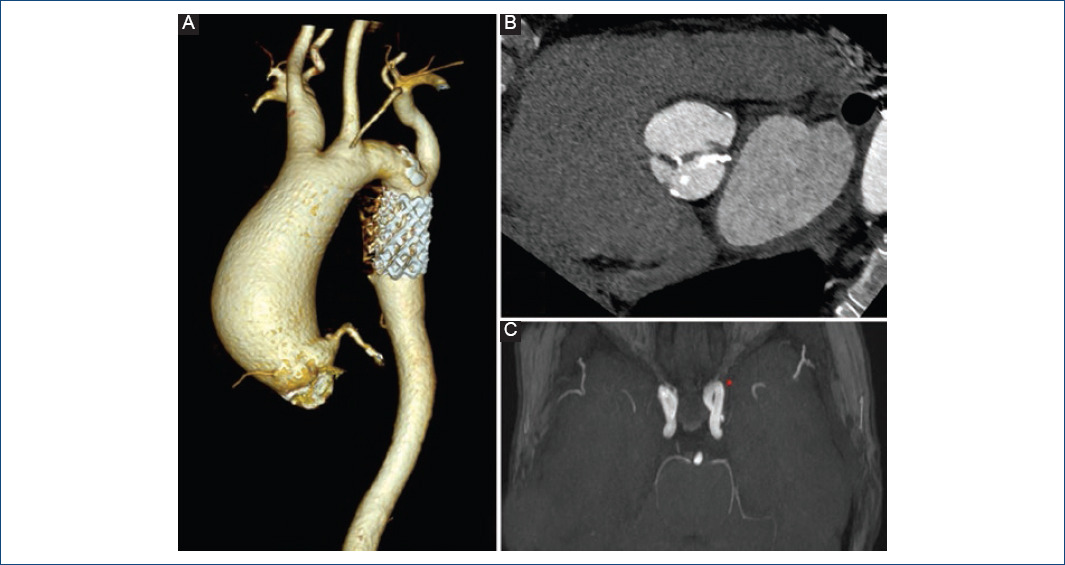

El desarrollo anómalo de la válvula bicúspide se integra, hoy en día, en las llamadas anomalías del tracto de salida del ventrículo izquierdo, incluida en este espectro junto con la coartación de aorta, el síndrome del corazón izquierdo hipoplásico, etc. Por ejemplo, aproximadamente el 50% de los pacientes con coartación asocian VAB3,13,15 (Fig. 2). Además, se observa una marcada heterogeneidad genética subyacente a la VAB, apareciendo ligada a distintas cromosomopatías y enfermedades genéticas13. Se ha descrito una mayor prevalencia de VAB en el síndrome de Down (trisomía 21) o en el síndrome de DiGeorge (monosomía 22q11), así como en el síndrome de Turner, con una prevalencia del 15-30% en pacientes con esta enfermedad; también en el síndrome de Marfan, en el de Loeys-Dietz y el de William-Beuren13. A pesar de que ha habido un gran interés durante las últimas décadas por descubrir los mecanismos que dan lugar a la formación de la valvulopatía bicúspide, los genes y las interrelaciones de las moléculas implicadas en el desarrollo normal del tracto de salida del ventrículo izquierdo no se conocen aún de forma adecuada. Se han relacionado con VAB varias vías de señalización que son clave en el desarrollo morfológico normal del corazón: superfamilia del factor de crecimiento tumoral beta (TGF-β), familia GATA, Tbx20, sintetasa 3 del óxido nítrico (eNOS3), NOTCH1 o Wnt/β-catenina, entre otros1,15,17,18. Se sabe que el desarrollo de la VAB no se debe a un solo gen, y actualmente, para una mejor clasificación de las mutaciones relacionadas, se distinguen dos grupos. Por un lado, existen alteraciones genéticas descritas en pacientes con VAB que se relacionan con síndromes clínicos, como por ejemplo las mutaciones en FBN1 (síndrome de Marfan) o en TGFBR1/2 (síndrome de Loeys-Dietz)18. Por otro lado, existen las alteraciones no sindrómicas, por ejemplo las mutaciones en GATA5, PITX2 o CLIP21,18. Entre las formas esporádicas o no sindrómicas, las mutaciones en el gen NOTCH1 son las más estudiadas. Se han descrito familias con mutaciones en este gen que se comporta con un patrón de herencia autosómica dominante. Las rutas de señalización de NOTCH1 están altamente conservadas entre especies, ya que tienen un papel fundamental en procesos de diferenciación celular, desarrollo celular y comunicación intercelular, y desempeñan una función crucial en la organogénesis embrionaria y en particular en el desarrollo del sistema cardiovascular18. Además, la inhibición de NOTCH1 conduce, a su vez, a una señalización defectuosa en la vía del TGF-β, existiendo una relación entre estas dos vías que afecta al correcto remodelado de la matriz vascular y al desarrollo correcto de la válvula aórtica. La familia GATA de factores de transcripción ha sido involucrada en los procesos de diferenciación celular18. Varios genes, GATA4, GATA5 y más recientemente GATA6, han sido relacionados con el desarrollo de VAB18-20. También la proteína óxido nítrico sintetasa (NOS) ha sido relacionada con la morfogénesis valvular. Concretamente, NOS-3, constitutiva del tejido vascular, presenta mutaciones relacionadas con el desarrollo de VAB18. No solo surgen con fuerza estudios genéticos, sino también epigenéticos (cambios heredables en la expresión génica sin cambios en la secuencia de ADN) en el ámbito de la VAB. Se han estudiado mecanismos relacionados con la metilación del ADN, modificaciones de histonas, etc. Un estudio demostró una hipermetilación de la región correspondiente a GATA4 y una hipometilación en ACTA2 en individuos con VAB, en comparación con sujetos controles21. También se han estudiado microARN y lncARN (ARN largos no codificantes) relacionados con la VAB. En un amplio estudio con microarrays, Yanagawa, et al.22 demostraron una expresión diferencial de 34 microARN comparando pacientes con VAB y válvula aórtica tricúspide (VAT), e identificaron el miR-141 como regulador de la calcificación acelerada valvular. A pesar de los grandes esfuerzos en los últimos años, con multitud de investigaciones en este campo del saber científico, aún se desconoce cuál es la base ontogenética del desarrollo de la VAB.

Figura 2 Paciente con aortopatía bicúspide y coartación de aorta intervenida en la edad adulta mediante implante de stent. A: reconstrucción tridimensional de tomografía computarizada (TC) que muestra un aneurisma de aorta ascendente y el stent en la zona de coartación. B: TC que muestra la válvula aórtica bicúspide con zonas de calcificación en sus velos. C: los pacientes con coartación de aorta pueden presentar aneurismas del polígono de Willis, por lo que se recomienda su cribado.